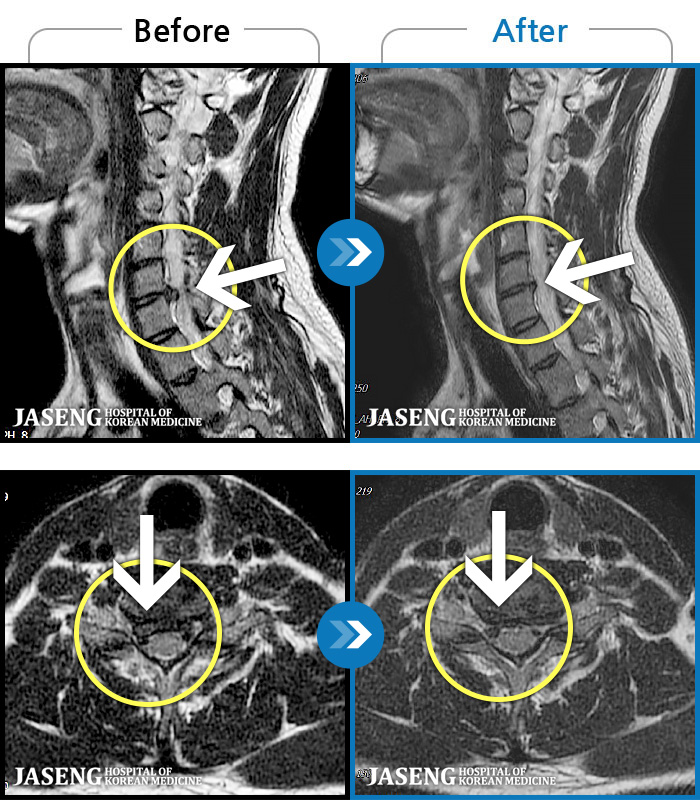

MRI ġ

56 MRI ũ ʸ Ȯϼ.